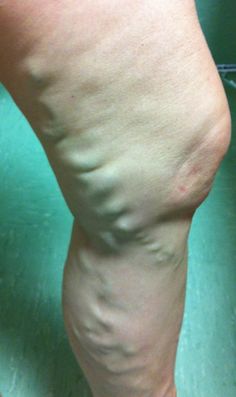

Ispezioni l’area. Non vedi niente a livello di coscia. A livello di gamba diversi gavoccioli varicosi. Palpi l’area della coscia che ti indica. Effettivamente le fa male. Ti sembra di palpare qualcosa di duro sotto… non c’è né rubor né calor però .. .

Però il dolore è ben localizzato alla superficie mediale della coscia, non la postero-laterale; Lasegue negativo bilateralmente. Non ha segni di cellulite. Ci starebbe pure quella con la difficoltà che deve avere di linfodrenaggio.

Inoltre, come nella nostra signora, ricordiamo che nei pazienti obesi la clinica di TVS è spesso insignificante in quanto le vene superficiali possono essere localizzate sotto diversi centimetri di adipe, quindi con una cute che permane perfettamente normale.